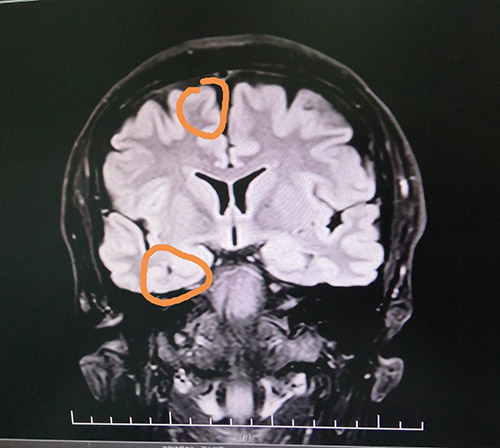

▲患者癫痫病灶区

蓝十字脑科功能神经外科主任杨忠旭博士认真查看了刘先生各项检查报告并听取相关病情汇报,认为患者脑组织结构发生病变,引起癫痫发作,经系统药物治疗无任何改善,应用现代神经影像学技术和电生理监测技术,能明确引起癫痫发作的的“责任病变”。

在征得患者家属同意后,10月28日上午,杨忠旭博士在助手杜立功及医护团队协助下为刘先生进行了“癫痫病灶切除术”手术。由于患者患有高血压、脑萎缩,脑血管异常脆弱,且局部脑组织结构异常,多处异常放电部位,为手术带来挑战,手术中需要格外小心。在全程脑电监测下,杨博士处之泰然,游刃有余,在助手密切配合下,为患者切除了颞叶、海马和额叶病灶。癫痫病灶切除后,再次监测脑区,无异常放电,手术成功。紧接着彻底止血,严密缝合硬脑膜,复位骨板……紧张的手术终于结束。